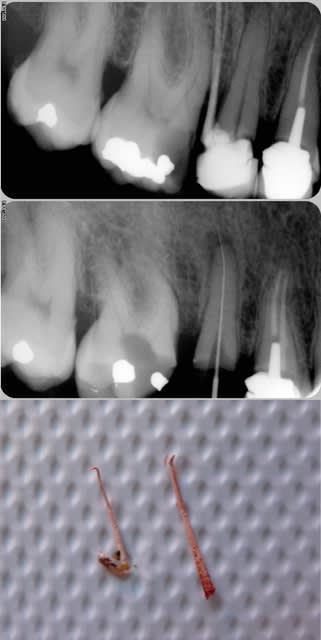

J'ai reçu, pour une première visite, une patiente motivée par un 'trou' dans une molaire, provoquant 'un bourrage gênant à nettoyer'.

Je prend un cliché.

J'ai pris un cliché de ce que j'ai sorti de l'espace inter-dentaire.

Il semble que ce soit une obturation 'radiculaire' (ou un double sondage paro avec cône) ??? !